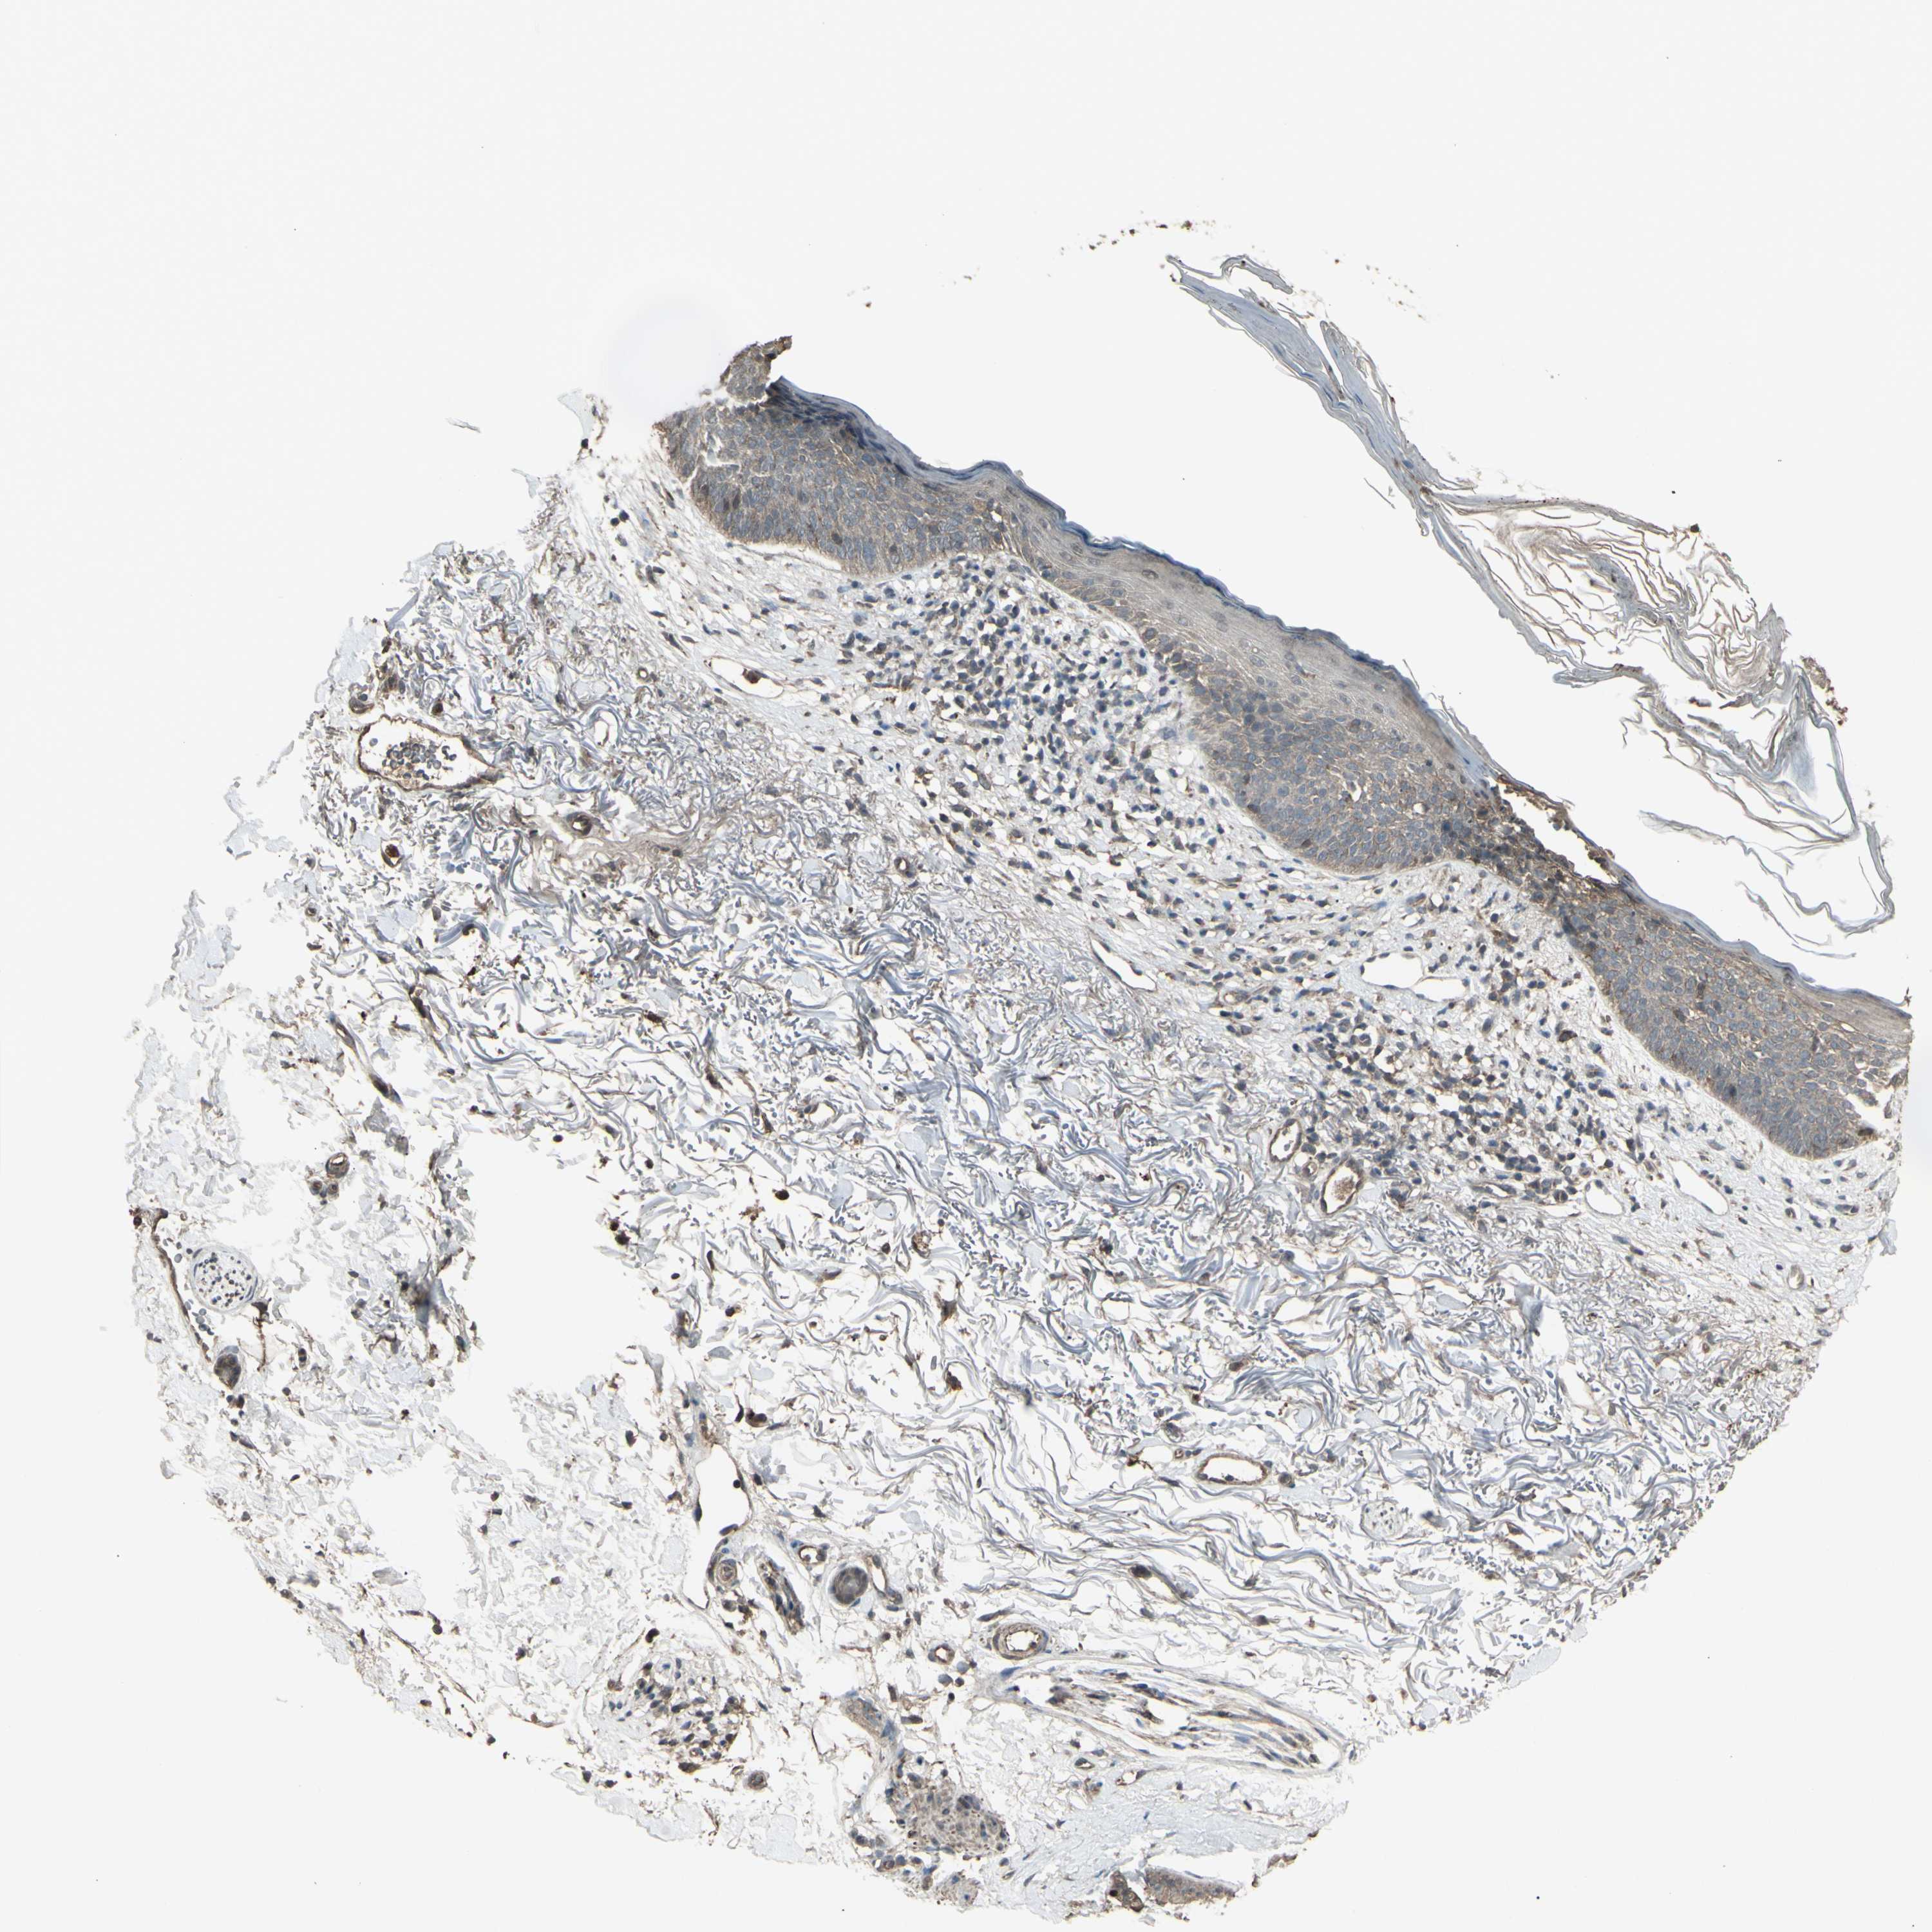

SKIN CANCER - Protein expressioni

A mouse-over function shows sample information and annotation data. Click on an image to view it in a full screen mode. Samples can be filtered based on level of antibody staining by selecting one or several of the following categories: high, medium, low and not detected. The assay and annotation is described here.

Each image is clickable and will lead to virtual microscopy that enables deeper exploration of all samples and also displays staining intensity scores, fraction scores and subcellular localization as well as patient and tissue information for each sample.

Antibody HPA028386

Squamous cell carcinoma, metastatic, NOS